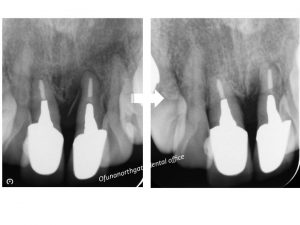

その時のレントゲンが以下です。

歯が完全に割れていました。

患者様はレントゲンの状況をみていただき、

ご納得の上、抜歯となりました。

現在はインプラント治療が完了し、噛めるようになっています。

患者様も抜歯後には、できるかぎり周囲の歯に負担がかからない治療をご希望されていたため、

歯を削るブリッジではなく、

インプラント治療をご希望されました。